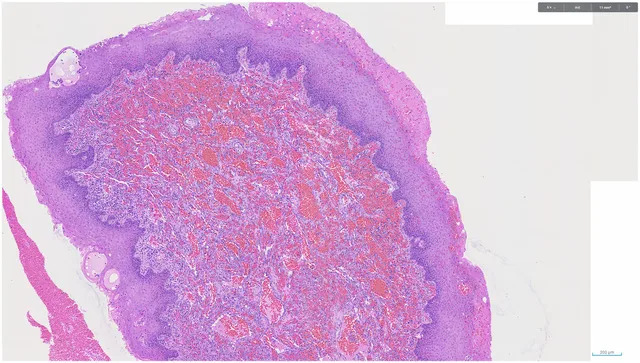

Imágenes:

1 H&E

Diagnóstico: SARCOMA DE KAPOSI, con intenso artefacto de cauterio en la muestra remitida.

- Microscópicamente, el sarcoma de Kaposi aparece como láminas de células fusiformes atípicas que forman espacios vasculares en forma de hendidura, que contienen eritrocitos extravasados. PMID: 21792787